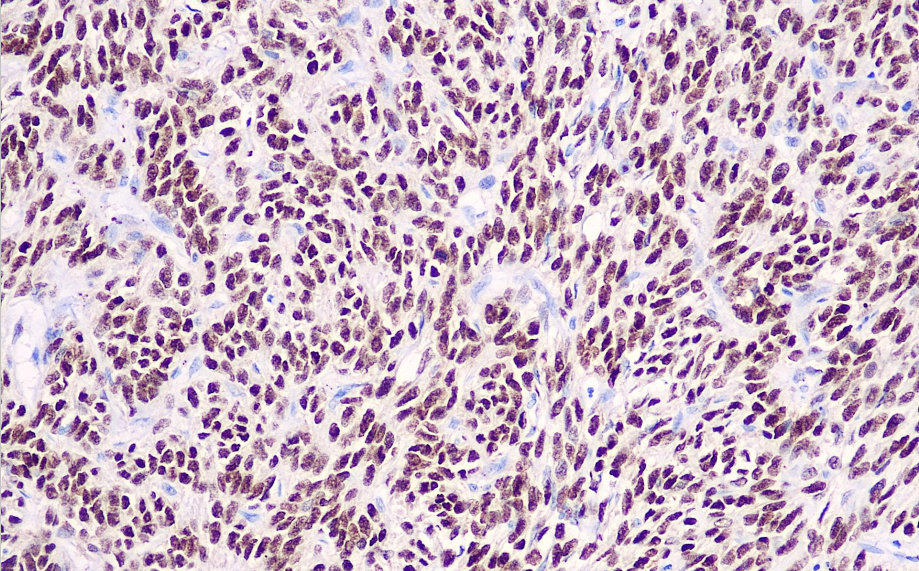

Positive control: synovial sarcoma

TLE1 is a member of the TLE multigene family and is involved in hematopoiesis, neuronal, and peripheral epithelial differentiation. It is expressed in synovial sarcoma but rarely in neurofibromas and pleomorphic sarcomas. Research data indicate that TLE1 expression in synovial sarcoma has higher sensitivity and specificity than Bcl2, and it is therefore recommended as a marker for synovial sarcoma.

The TLE1 antibody reagent specifically binds to the TLE1 molecular antigen. The immunohistochemistry kit containing the TLE1 antibody reagent is suitable for the precise diagnosis of synovial sarcoma.